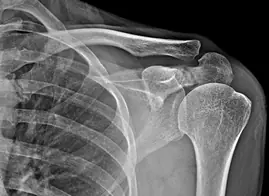

Luxations gleno-humerales